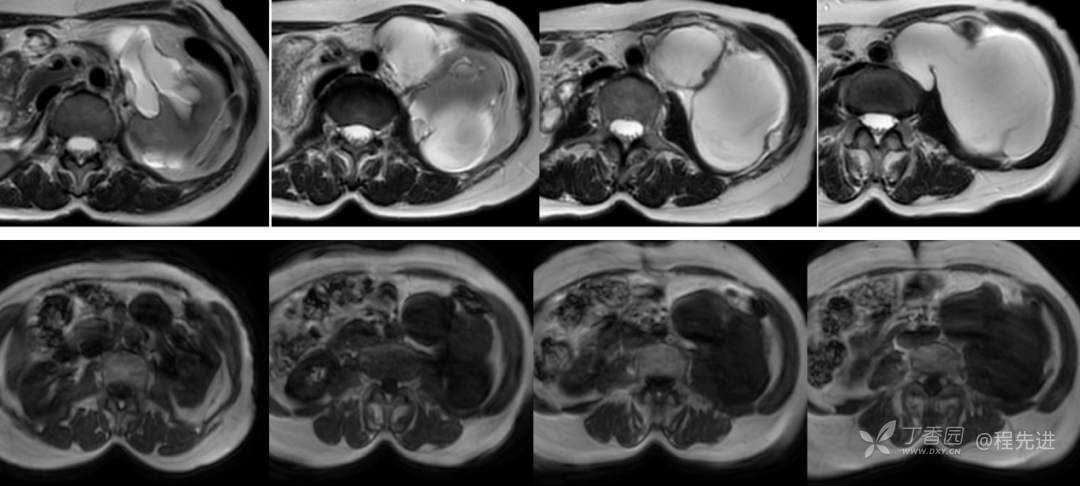

MR平扫: